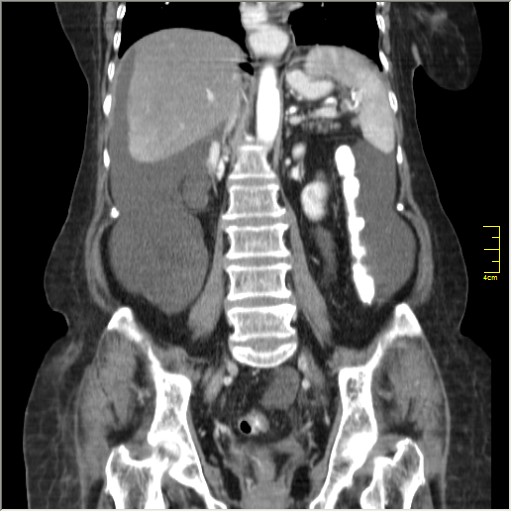

Женщина 72 года. Поступила с жалобами на вздутие живота. После осмотра хирургом, была сразу направлена на КТ брюшной полости.

Итак, асцит с объёмным образованием таза. В данном случае можно быть более конкретным, у пациентки неоплазия правого яичника с региональной лимфаденопатией (увидели?) и выраженным асцитом, характерным именно для злокачественных опухолей яичников. Пациентка оперирована ( операция Вертгейма); диагноз верифицирован: аденокарцинома правого яичника (серозная). Направлена к онкологу для дальнейшего лечения.